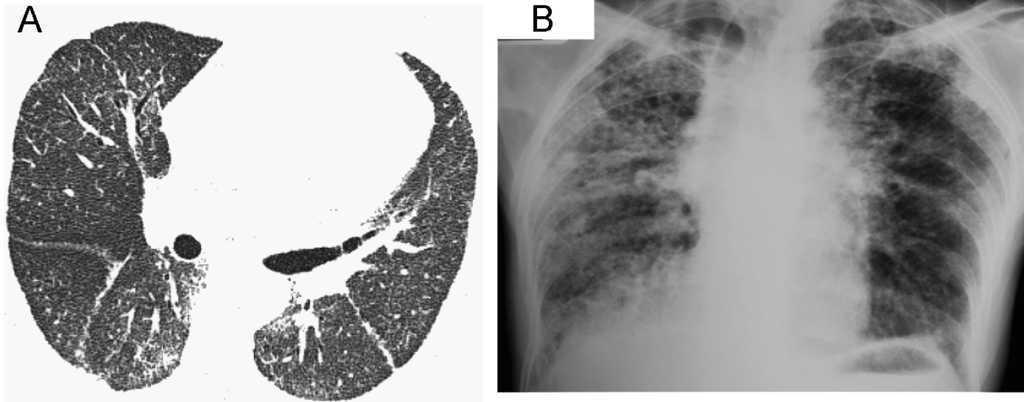

Figura 1. La tomografía computarizada de alta resolución (A) muestra una imagen discreta y difusa de vidrio deslustrado, así como opacidades reticulares periféricas y en parche. No se aprecia panal de abeja. La radiografía de tórax (B) demostró disminución de los volúmenes pulmonares e infiltrados reticulonodulares de predominio apical, así como panal de abeja periférico y bibasal con ensanchamiento de la arteria pulmonar.

Observación clínicaCaso 1Mujer de 60 años, albina, con epistaxis y púrpura de 2 años de evolución. Un año antes de acudir a consulta había comenzado a presentar disnea al ejercicio y tos no productiva. Las pruebas de función pulmonar mostraron un grave patrón restrictivo, con capacidad vital forzada del 42%, volumen espiratorio forzado en el primer segundo del 50% y capacidad de difusión de monóxido de carbono del 60% del predicho. La tomografía computarizada de alta resolución (figura 1A) mostró una imagen discreta y difusa de vidrio deslustrado, así como opacidades reticulares en parche sin panal de abeja. La biopsia de pulmón a cielo abierto demostró neumonitis intersticial fibrosante, de predominio subpleural, panal de abeja microscópico y focos de fibroblastos. Había áreas de pulmón normal adyacentes a las zonas de pulmón con fibrosis. Además se observaron áreas de neumonía organizada en parche, así como proliferación y vacuolización de neumocitos tipo 2 con zonas de bronquiolitis constrictiva y metaplasia bronquiolar o lambertosis. Estos hallazgos eran indicativos de neumonía intersticial usual, pero con características especiales (figura 2). Dada la presencia de albinismo, se realizó una aspiración de médula ósea que mostró megacariocitos llenos de gránulos densos y cuerpos de lipofuscina, lo que permitió confirmar el diagnóstico de SHP. La paciente presentó un curso agresivo y progresivo de la disnea, y murió un mes después.

Caso 2Mujer de 56 años, con albinismo oculocutáneo, hermana de la paciente anterior, a quien se examinó en nuestra institución 10 años antes de tratar al caso 1. Acudió a consulta con una historia de 10 meses de evolución de disnea al ejercicio, tos seca y dolor torácico. Desde hacía 3 años presentaba diátesis hemorrágica caracterizada por epistaxis, hematomas y gingivorragia. Se le realizó una espirometría que reveló un grave patrón restrictivo, con capacidad vital forzada del 31% y volumen espiratorio forzado en el primer segundo del 37% del predicho. Los estudios de laboratorio hematológicos demostraron que tanto las plaquetas como los tiempos de coagulación estaban dentro de los límites normales. La radiografía de tórax demostró disminución de los volúmenes pulmonares e infiltrados reticulonodulares de predominio apical, así como panal de abeja periférico y bibasal con ensanchamiento de la arteria pulmonar (figura 1B). Debido a lo avanzado del daño pulmonar no fue posible realizar biopsia pulmonar a cielo abierto. Se le administró tratamiento con oxígeno, el curso fue progresivo y la paciente murió un mes después de acudir a consulta.